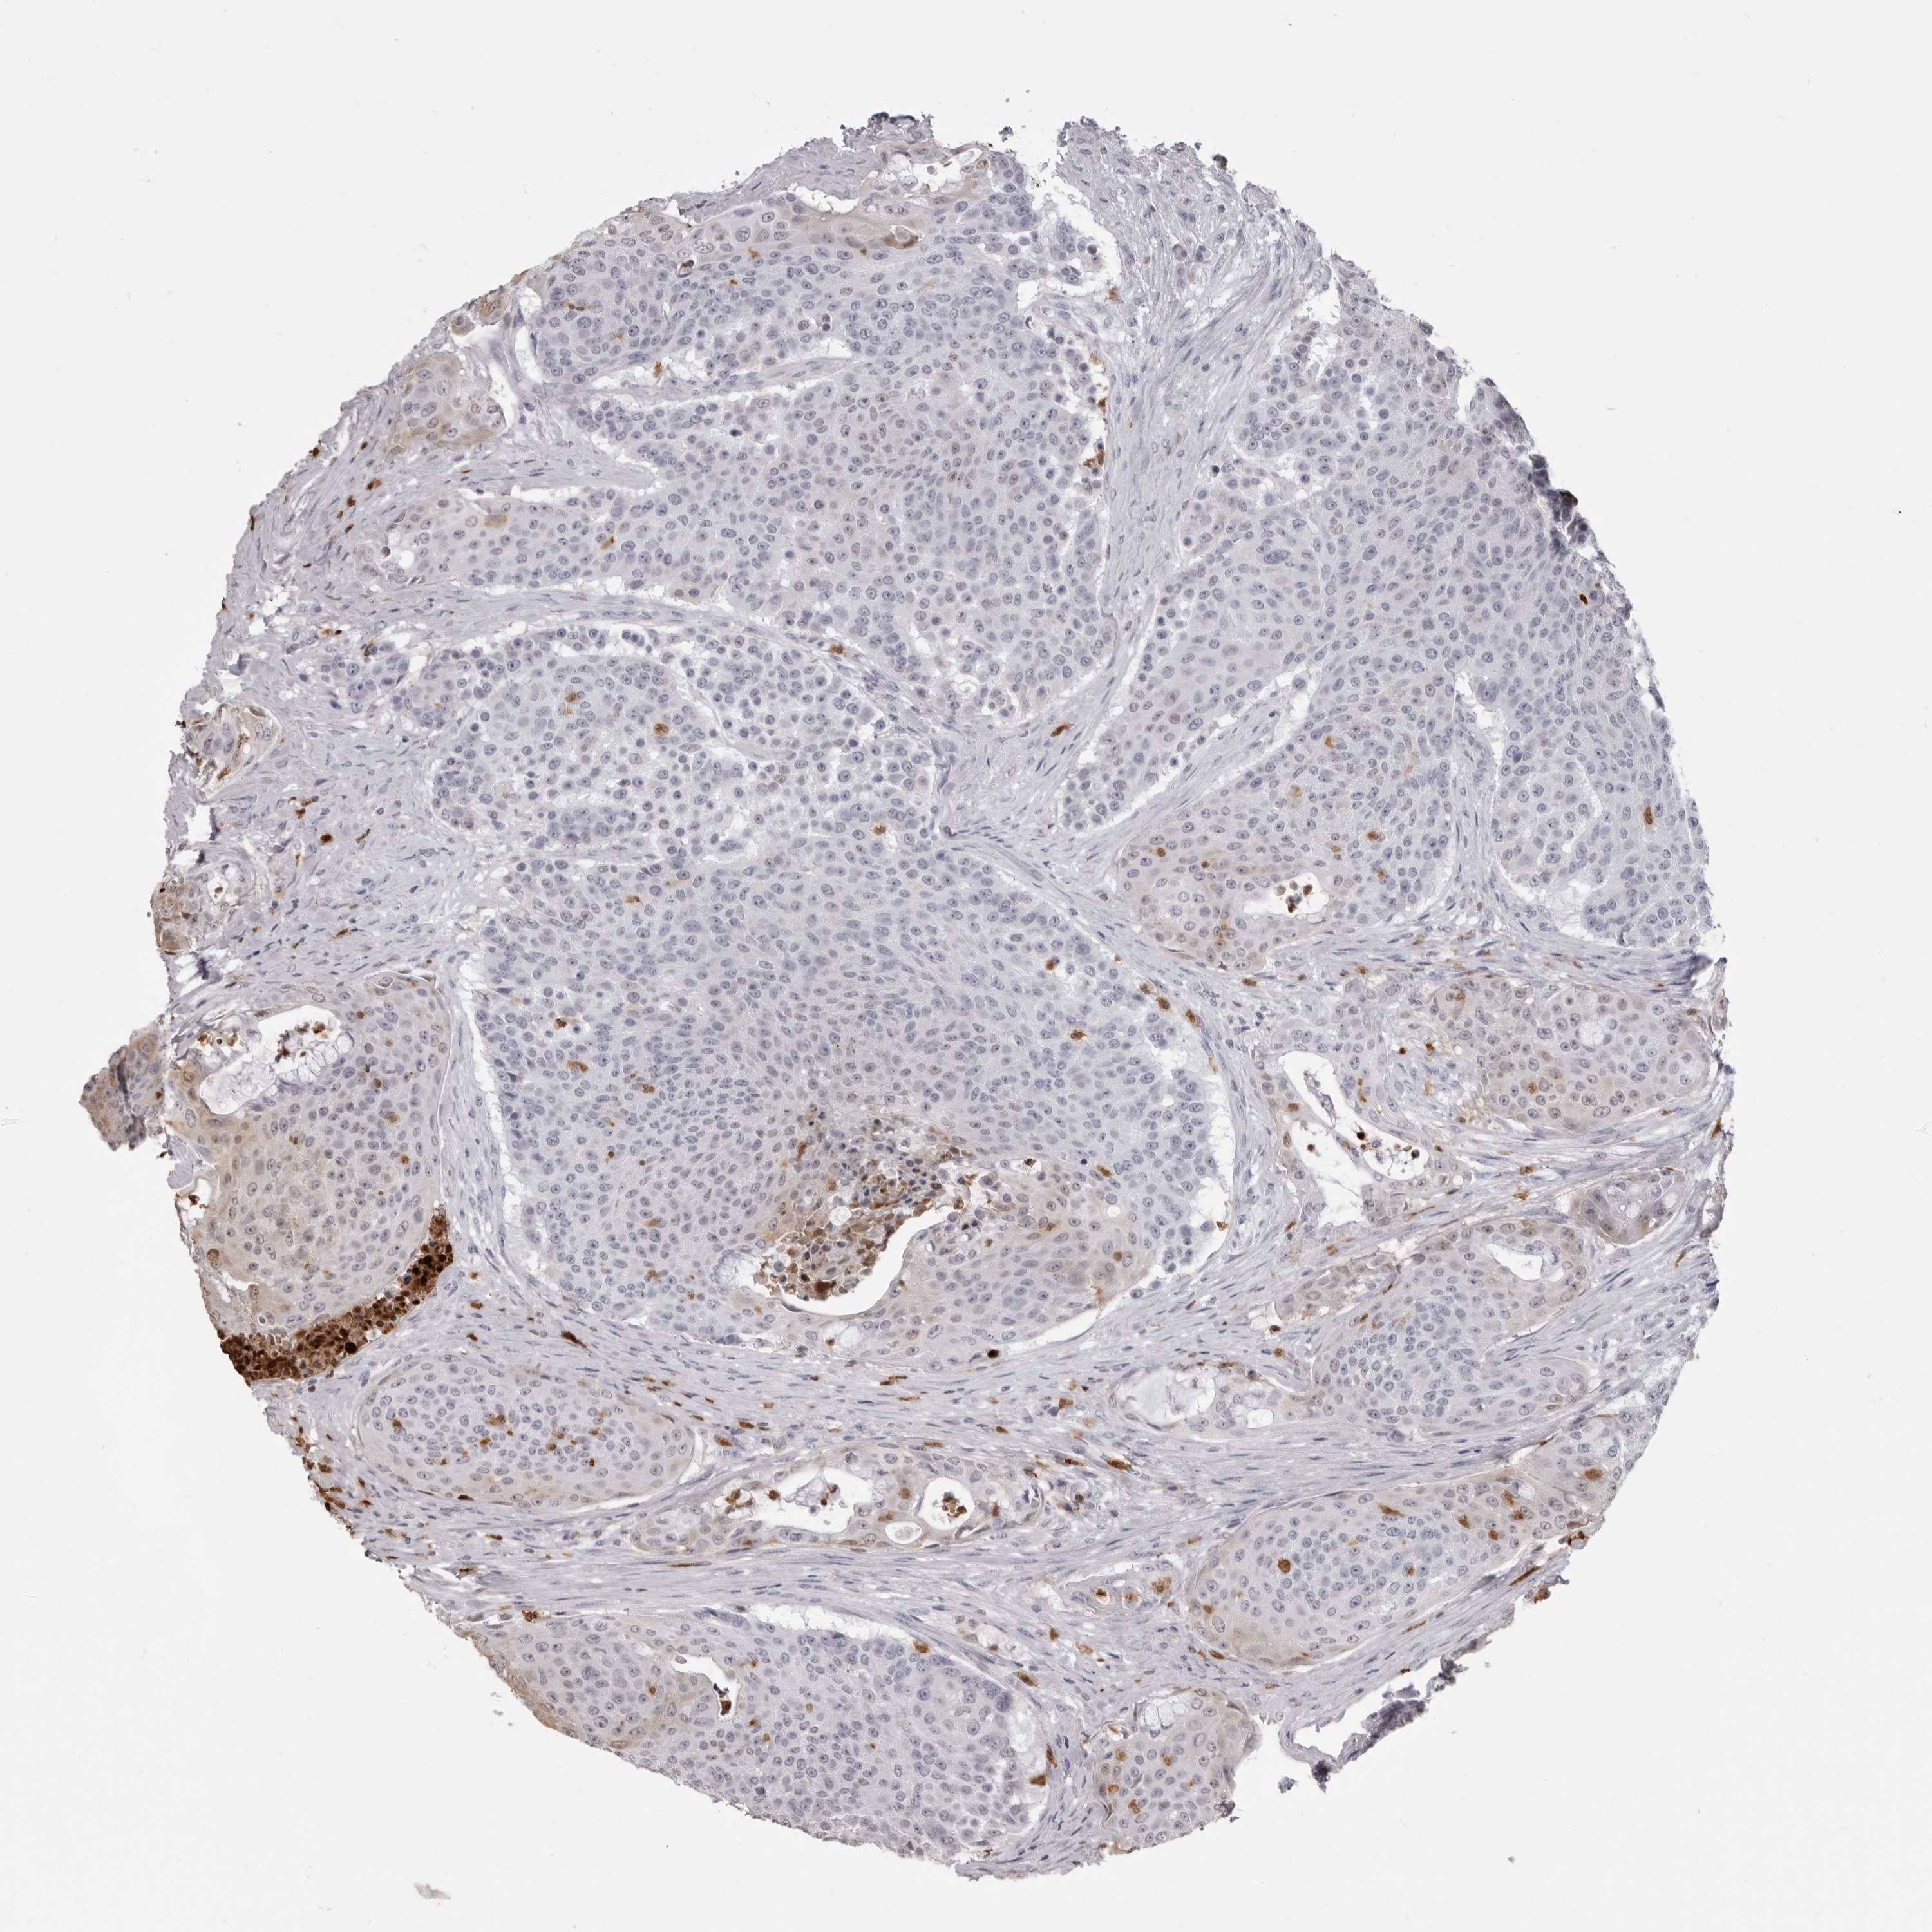

UROTHELIAL CANCER - Protein expressioni

A mouse-over function shows sample information and annotation data. Click on an image to view it in a full screen mode. Samples can be filtered based on level of antibody staining by selecting one or several of the following categories: high, medium, low and not detected. The assay and annotation is described here.

Note that samples used for immunohistochemistry by the Human Protein Atlas do not correspond to samples in the TCGA dataset.

Antibody stainingi

Antibody staining in the annotated cell types in the current human tissue is reported as not detected, low, medium, or high, based on conventional immunohistochemistry profiling in selected tissues. This score is based on the combination of the staining intensity and fraction of stained cells.

Each image is clickable and will lead to virtual microscopy that enables deeper exploration of all samples and also displays staining intensity scores, fraction scores and subcellular localization as well as patient and tissue information for each sample.

Antibody CAB025657

Staining

High

Medium

Low

Not detected

Intensity

Strong

Moderate

Weak

Negative

Quantity

>75%

75%-25%

<25%

None

Location

Nuclear

Cytoplasmic/membranous

Cytoplasmic/membranous,nuclear

Urothelial carcinoma, Low grade

Urothelial carcinoma, High grade